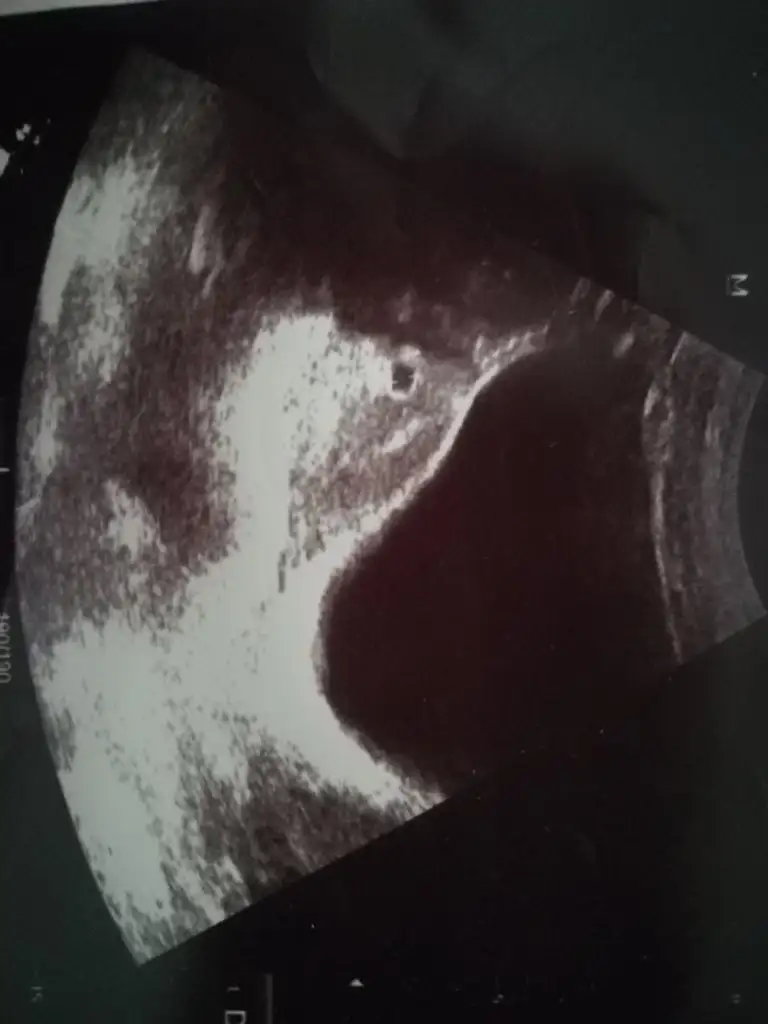

Sağdaki bebiş Ramzi teorisine göre kız hayırlısı bakalım

evet canım ikra meyrada öyle demişti bir kızım vvar ama hayırlısıSağdaki bebiş Ramzi teorisine göre kız hayırlısı bakalım

Bu kadar erken anlaşılıyor mu harikaSağdaki bebiş Ramzi teorisine göre kız hayırlısı bakalım

Sadece teori canım tutmayan da tutan daBu kadar erken anlaşılıyor mu harika